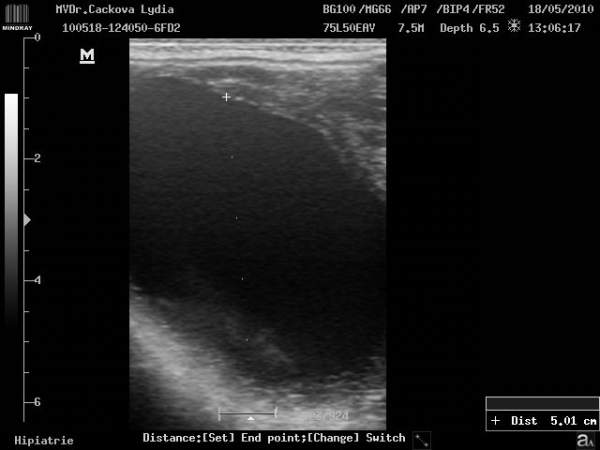

ultrasonografické vyšetření klisny

Preovulační folikul